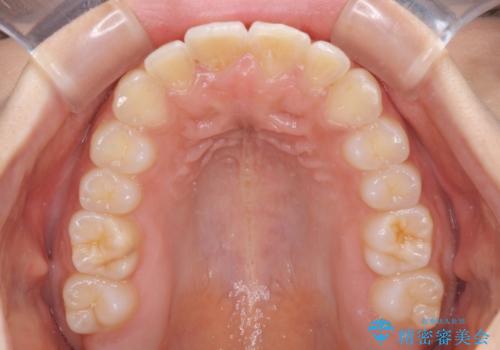

大きなトラブルもなく、順調に歯列が整ったため、僅か9ヶ月で装置を外すことができました。

あまりに短期間であったため、患者様自身も非常に驚いていらっしゃいました。

- 飛び出した前歯と全体的なデコボコを気にして来院された患者様です。